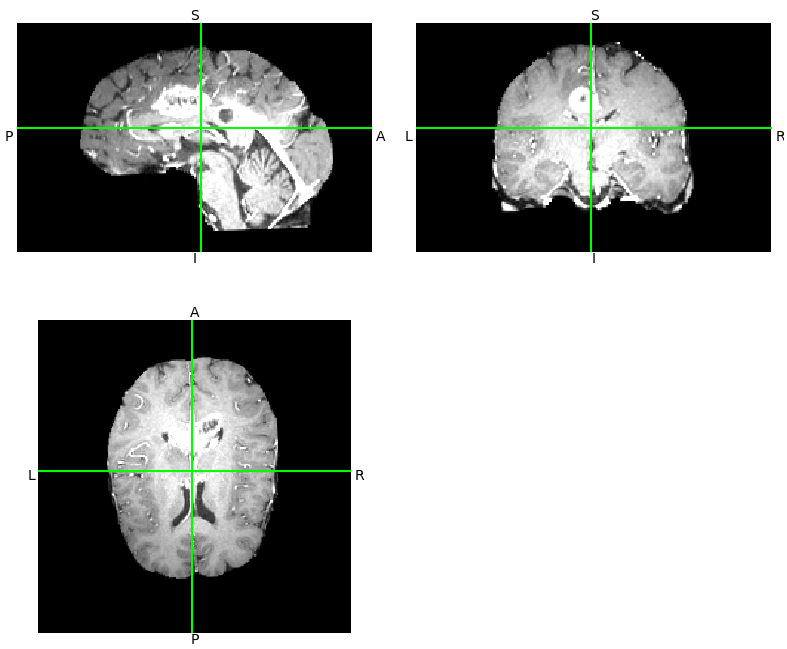

3.1 读取.nii.gz文件获取三维视角

import matplotlib

matplotlib.use('TkAgg')

from matplotlib import pylab as plt

import nibabel as nib

from nibabel.viewers import OrthoSlicer3D

example_filename = './fixed.nii.gz'

img = nib.load(example_filename)

OrthoSlicer3D(img.dataobj).show()